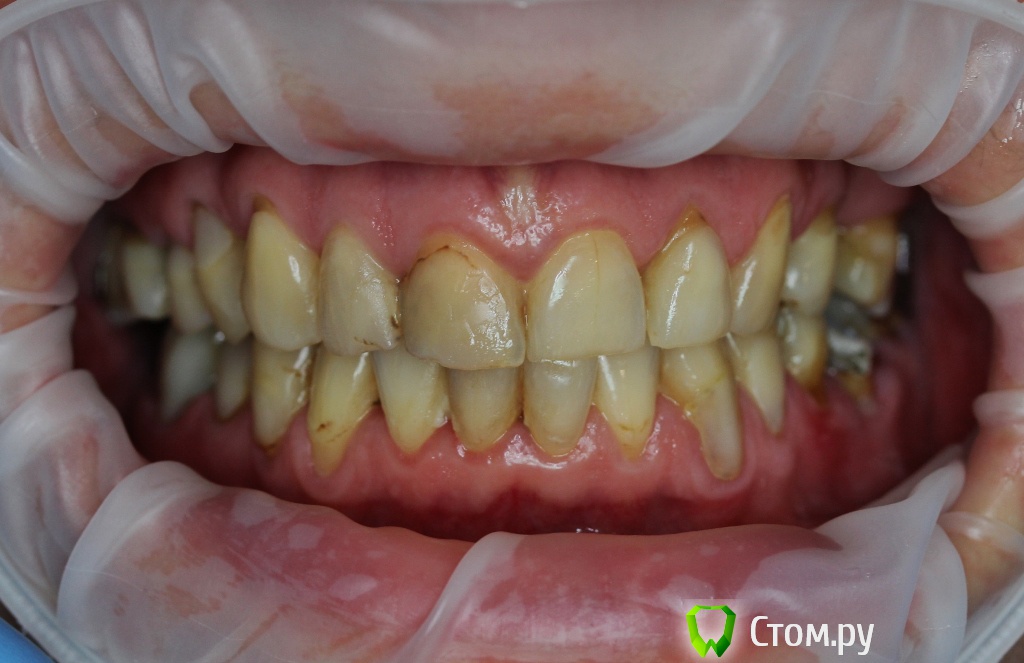

Dr.Sham Опубликовано 21 октября, 2014 Поделиться Опубликовано 21 октября, 2014 (изменено) Пациентка 55 лет с онкологией в прошлом.Аутоиммунный тиреоидит.Хочет красивые зубы, которыми можно жевать.Суставной компонент я не диагностирую, щелчков и посторонних шумов при открывании рта нет. Мышцы без гипертонуса, пальпаторно боли отмечает со стороны крыловидной медиальной и латеральной мышц слева.Фотки. Рентген. КТ пока не делал, хочется сделать с шаблоном, но пока с планом лечения не определились.Брекеты не хочет, каппы хочет, но я не знаю возможности лечения на каппах и доктора ответственного (С-Пб.) Фото: Модели в артикуляторе: ОПТГ Изменено 21 октября, 2014 пользователем Dr.Sham Ссылка на комментарий

Slaggy Опубликовано 21 октября, 2014 Поделиться Опубликовано 21 октября, 2014 (изменено) Суставной компонент я не диагностирую, щелчков и посторонних шумов при открывании рта нет. Мышцы без гипертонуса, пальпаторно боли отмечает со стороны крыловидной медиальной и латеральной мышц слева. "На глазок" - слева уровень ВЧ вырезки выше на 1 мм, значит сустав компенсирует этот мм. Вот вам и боли при пальпации.Если планируете тотал, сделайте МРТ суставов или аксиографию. Подстрахуйтесь.Возможно там хроника без обострений (сустав). А если по оптг смотреть (хоть это неверно "в корне") уровень носового хода, пазухи, альвеолярного отростка слева так-же выше на 1-2 мм - скорее всего в суставе найдете патологию, как минимум слева. Изменено 21 октября, 2014 пользователем Slaggy Ссылка на комментарий

Dr.Sham Опубликовано 21 октября, 2014 Автор Поделиться Опубликовано 21 октября, 2014 Доктора, спасибо за ответы, но ощущение, что комментировали одни терапевты.По существу: как можно помочь со скученностью, каковы причины рецессий, клинов на всех зубах, какую окклюзионную схему выстроить? Пролечить или удалить - это все понятно. Пролечили - удалили. В боковых отделах зубо-альвеолярные выдвижения - может и лечить не стоит. Если ортодонтическое лечение на каппах возможно, то кроме скученности в переднем отделе может оно решить проблемы в боковых отделах? Ссылка на комментарий

Dr.Sham Опубликовано 22 октября, 2014 Автор Поделиться Опубликовано 22 октября, 2014 (изменено) Что Вы гадаете всё время? Вы померяли недостаток места во фронтальном отделе н/ч? Сможете Вы его компенсировать сепарацией? Если да, то нет разницы чем ровнять. Сделать интрузию боковых зубов позволит их пародонт? Вы продонтальный зонд брали в руки, а то об этом нет ни слова? Вы можете уже сказать какие зубы удалите, а какие останутся? Вот когда дадите ответы на эти вопросы, можно будет пойти дальше.Я не очень понимаю, как измерить недостаток места во фронтальном отделе нижней челюсти. Про интрузию тоже не знаю, каковы показания/противопоказания для этой манипуляции. Это должны решить пародонтолог и ортодонт? К сожалению, их в клинике нет. Если бы я сам знал все ответы на эти вопросы, то, наверное, и не постил бы эту тему здесь. а постил бы до и после. По теме: 36, 37 удалены, 38 - кандидат, 16 с трещиной тоже под удаление, 26 - с учетом всех проблем так же на выход. Остаются две верхние семерки - сильно выдвинутые. Вот я и спрашиваю, есть ли смысл их вколачивать? 46 с неадекватной непрямой реставрацией, думаю, под реставрацией безферрульный зуб будет. Так что, предполагаю, что в боковых отделах зубы будут удалены. Изменено 22 октября, 2014 пользователем Dr.Sham Ссылка на комментарий

M@estro Опубликовано 22 октября, 2014 Поделиться Опубликовано 22 октября, 2014 Отправьте пациента к пародонтологу на консультацию,если сами не справитесь. Аналогично с ортодонтом и хирургом. Бюджет у пациента выдержит тотальную работу,или имакс во фронтальные и нейлон ? С гигиеной не супер, на фоне анамнеза - вопрос о прогнозе хирургии. 4.6 на удаление,думать нечего. Ссылка на комментарий